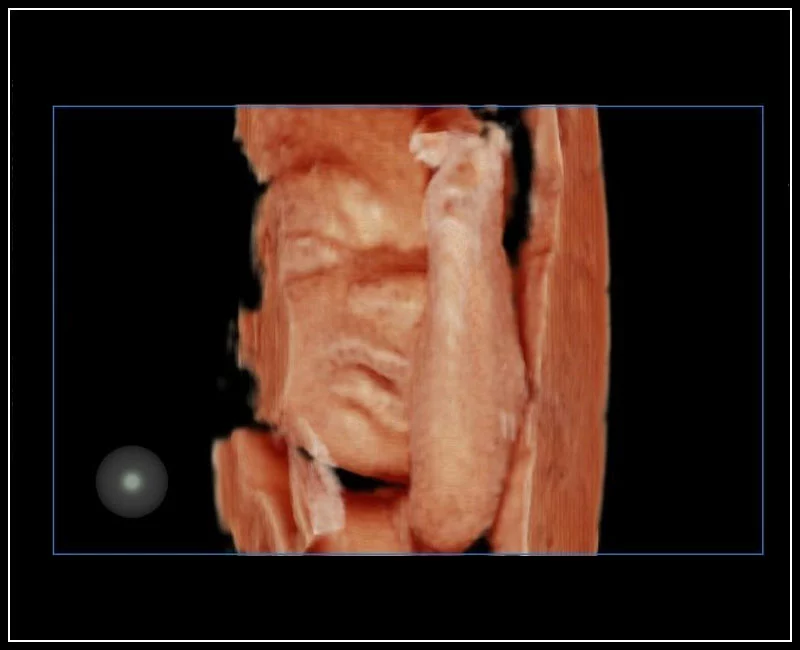

MyLab™E80 - 3D - Baby Face

MyLab™E80 - 3D - Baby Face

MyLab™9 Platform - Real-time baby face with 4D imaging

MyLab™9 Platform - Real-time baby face with 4D imaging

MyLab™9 Platform - Baby Face rendering in real-time with XLight

MyLab™9 Platform - Baby Face rendering in real-time with XLight

MyLab™A70 - Baby face

MyLab™A70 - Baby face

MyLab™C25 - Baby face

MyLab™C25 - Baby face